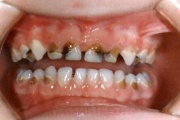

Lutipudelikaariese kahjustused

Lutipudelikaaries